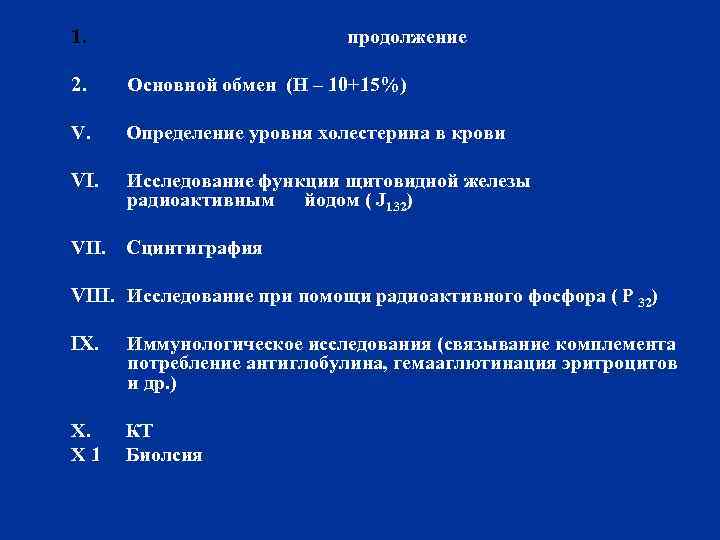

1. продолжение 2. Основной обмен (H – 10+15%) V. Определение уровня холестерина в крови VI. Исследование функции щитовидной железы радиоактивным йодом ( J 132) VII. Сцинтиграфия VIII. Исследование при помощи радиоактивного фосфора ( Р 32) IX. Иммунологическое исследования (связывание комплемента потребление антиглобулина, гемааглютинация эритроцитов и др. ) X. КТ X 1 Биолсия

1. продолжение 2. Основной обмен (H – 10+15%) V. Определение уровня холестерина в крови VI. Исследование функции щитовидной железы радиоактивным йодом ( J 132) VII. Сцинтиграфия VIII. Исследование при помощи радиоактивного фосфора ( Р 32) IX. Иммунологическое исследования (связывание комплемента потребление антиглобулина, гемааглютинация эритроцитов и др. ) X. КТ X 1 Биолсия